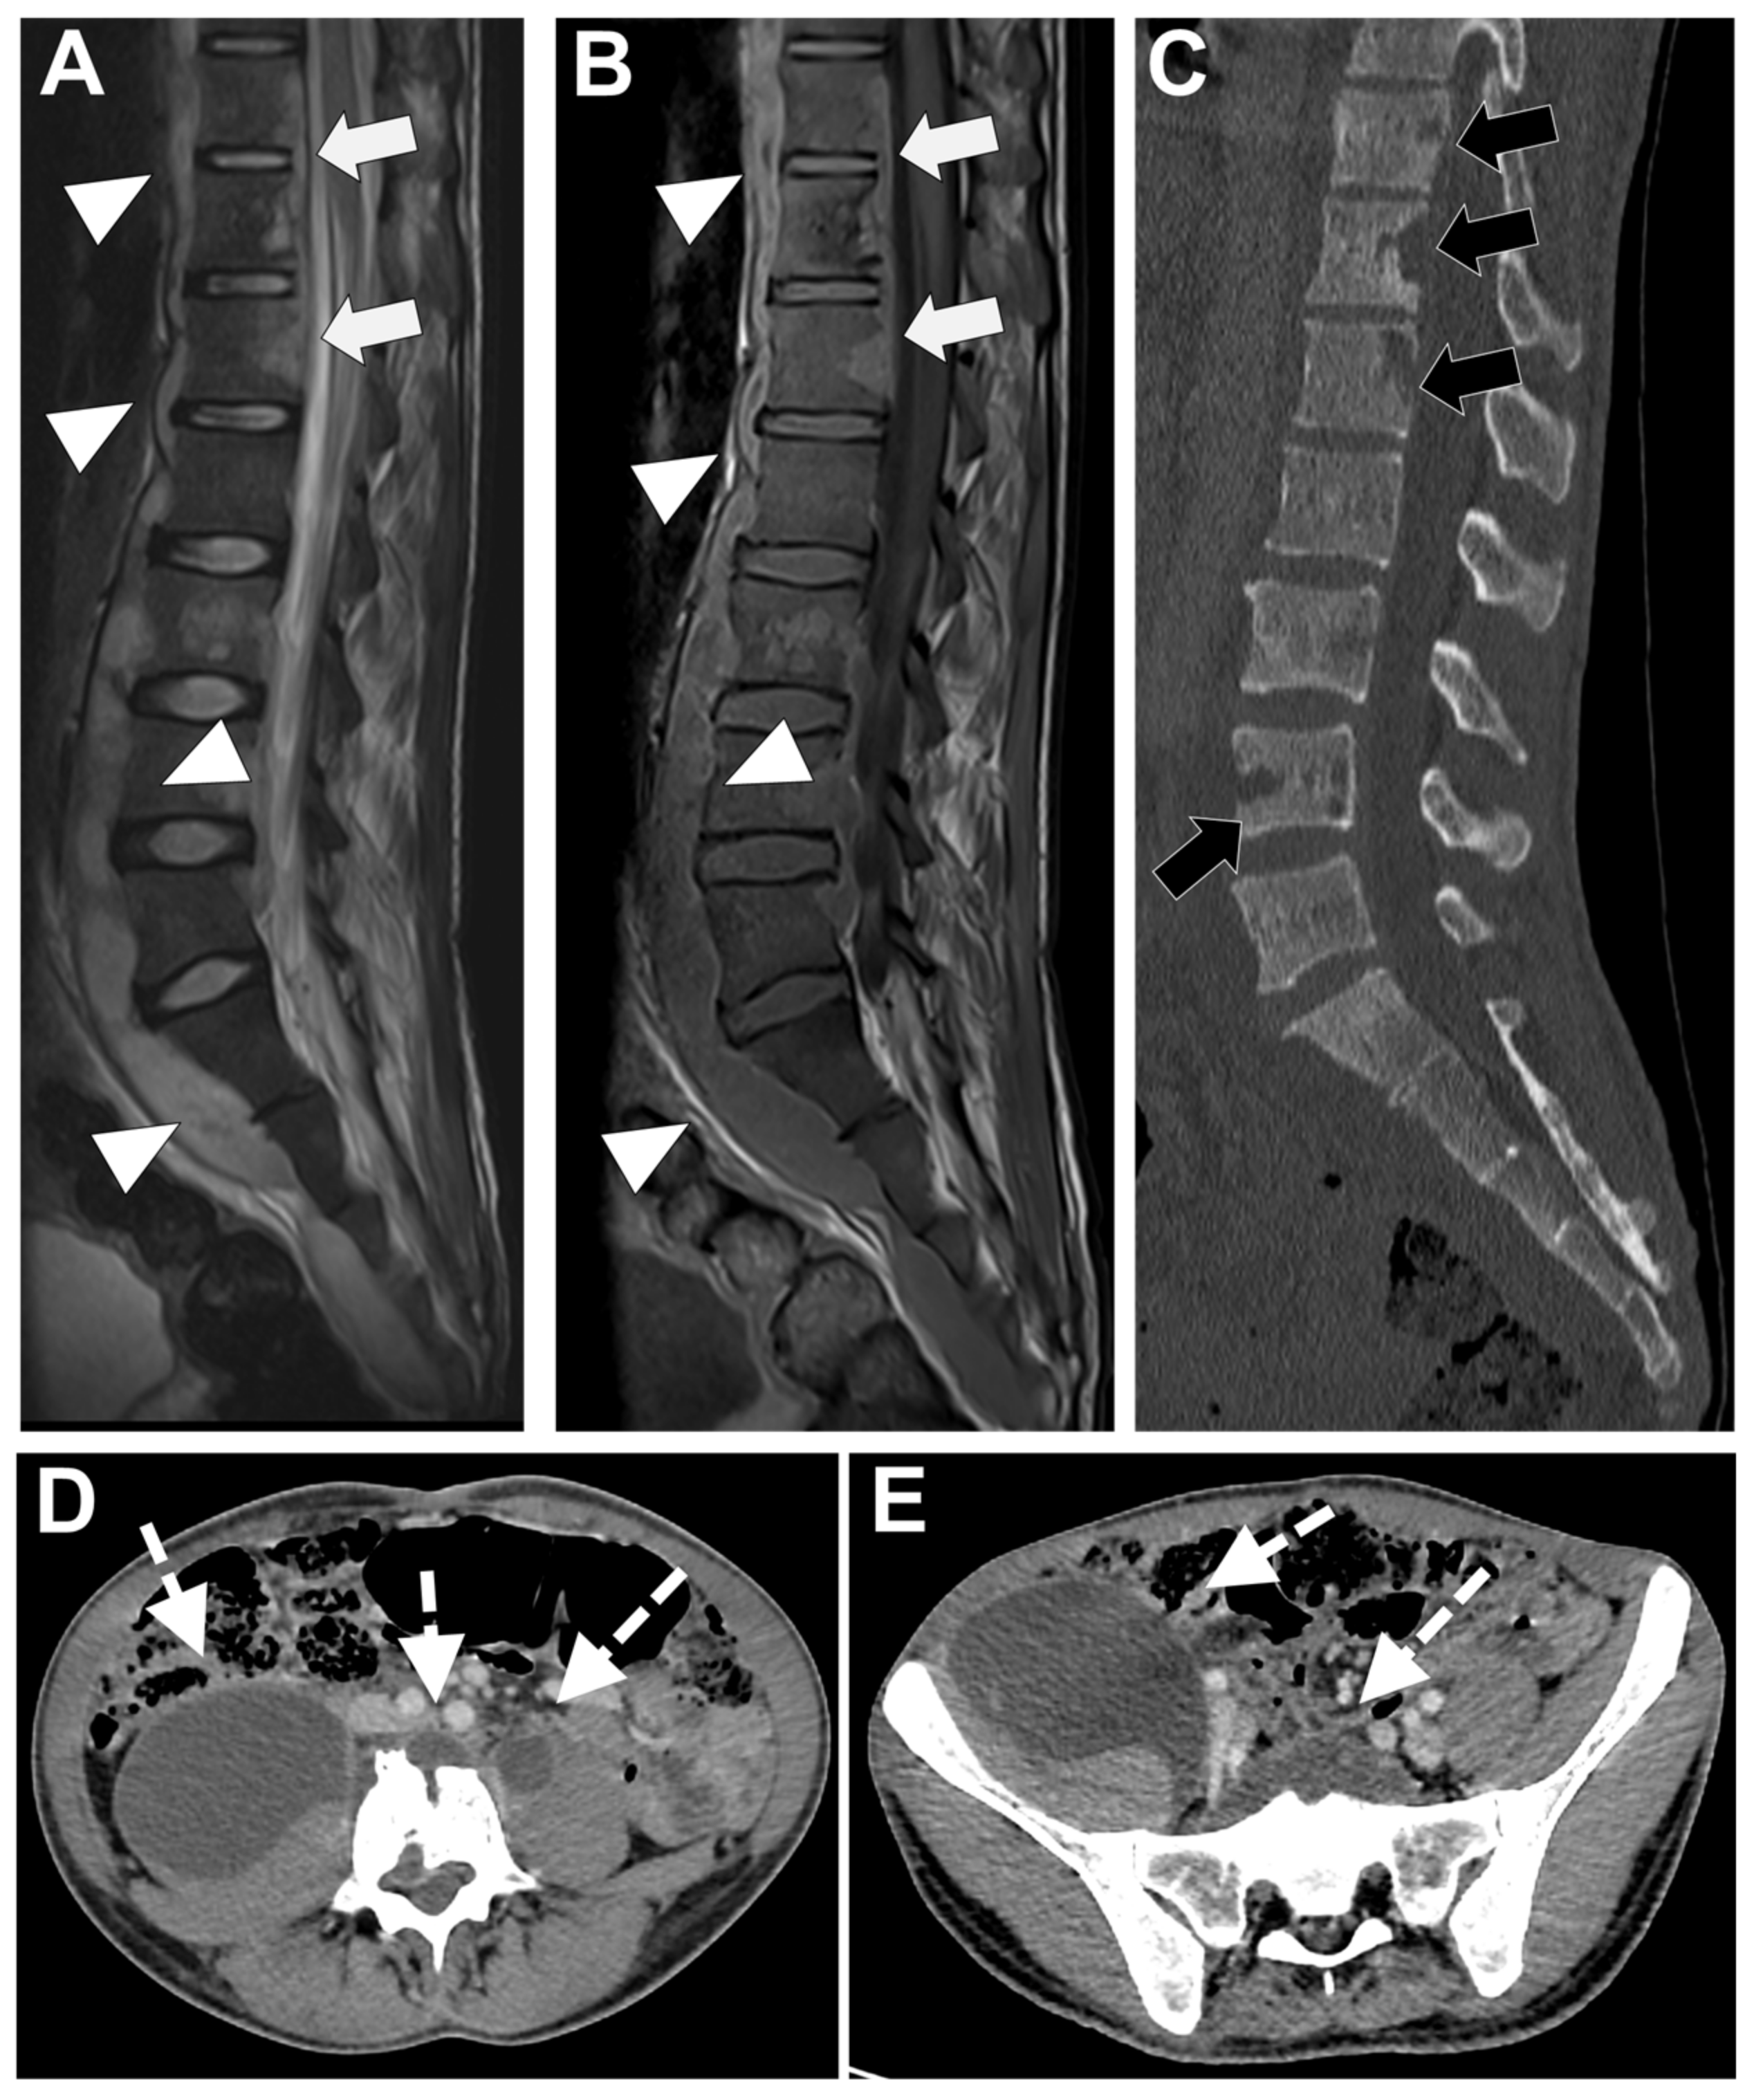

In Figure 7 an exemplificative case of PyS is presented.

Figure 7. A 73-year-old male presented with a rapidly evolving lumbar pain and fever, with an inflammatory syndrome on blood samples. A first MRI was performed as infectious spondylodiscitis was suspected, which included (A) STIR T2-weighted imaging (WI) and (B) fat sat T1-WI after gadolinium chelates injection. It shows a high signal intensity (SI) of the L3-L4 disc while other disks are in lower signal (black arrowhead), as well as linear subchondral contrast enhancement (CE) of the L3-L4 endplates both linear and more pronounced at the upper anterior corner of the L4 vertebral body (white arrowheads). Moreover, the left T11-T12 facet joints displayed marked edema of the subchondral bone and surrounding tissues (white arrows). A control MRI with SITR T2-WI (C) and fat-suppressed CE-T1-WI (D) was performed one month later, demonstrating a marked narrowing of the L3-L4 disk (black arrowhead), erosions of the vertebral body (dashed white arrows), extensive edema in the L3 and L4 vertebral body (white arrowhead), a persisting arthritis involving the left T1-T12 facet joint. Bacillus cereus was found on the Bacterial analysis of the L3-L4 disk biopsy.